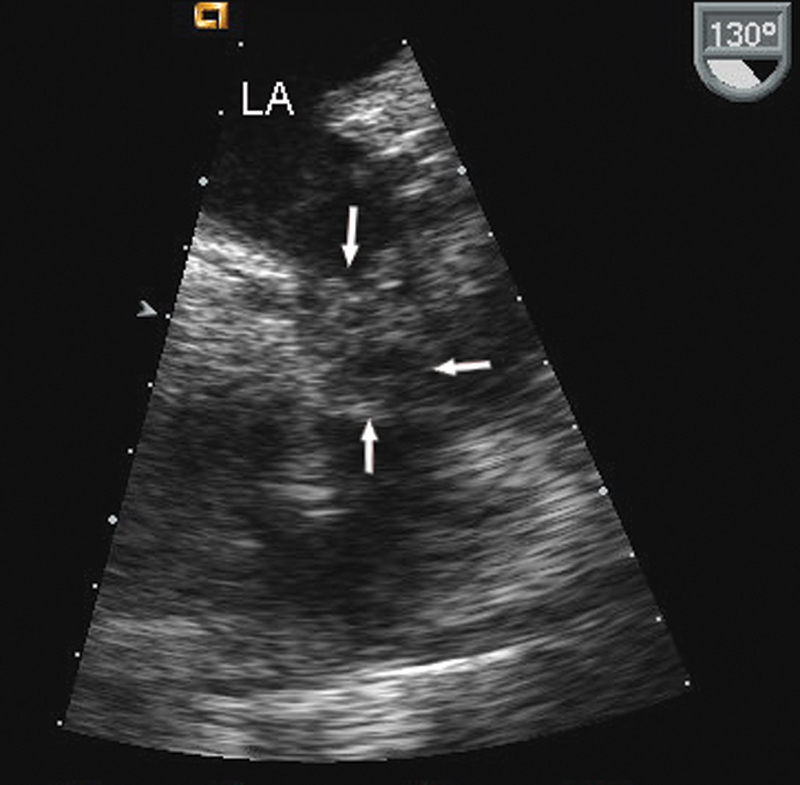

فحوصات تشخيصية لبعض امراض القلب والشرايين التاجية